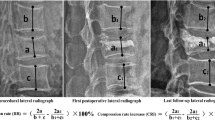

All measurements were done using PACS imaging display software (Centricity RA1000, GE Healthcare, Taipei, Taiwan). Two radiologists (W.C.L. and H.L.C.) measured the images. The lines for measurement were stored and confirmed by another radiologist, and agreement was reached by consensus. Digital files of pre-vertebroplasty, post-vertebroplasty, and follow-up radiographs were retrieved for measurement of the height of the anterior aspects of the collapsed vertebral body, and the height of the posterior border of an adjacent normal vertebral body. The height of the anterior border of the collapsed vertebral body was measured using standard methods [6]. To correct for possible differences in magnification ratio on the radiographs acquired before and after vertebroplasty, the ratio of the height of the collapsed vertebral body at the anterior border on the lateral view to that of the posterior border of an adjacent normal vertebral body was used as a reference. Differences in AVH within 1 mm were considered unchanged [5] to avoid biases from technical factors or inappropriate measurement.

The signal intensity (SI) of the five most central slices of the sagittal MRI was analyzed by two radiologists (W.C.L. and H.L.C.). The analysis included the injured and normal vertebrae above and below the injured vertebra in T1-weighted and T2-weighted images, and in T1-weighted Gd-DTPA-enhanced fat-suppression images. The normal vertebrae without apparent height loss and normal fatty marrow intensity were selected for analysis. Regions of interest (ROIs), covering the entire vertebrae, were identified manually in the intravertebral body area carefully so as not to contain the cortex. In T1-weighted Gd-DTPA-enhanced fat-suppression images, the SI of the well-enhanced zone, the poorly enhanced zone, and the whole of the injured vertebral body were measured. The area of each ROI was summed to yield a volume in the well and poorly enhanced zone, and the whole of the injured vertebral body. The standardized T1-, T2-weighted, and enhanced T1-weighted fat-suppression SI of the injured vertebral body was obtained by dividing the SI of the injured vertebral body by the SI of the normal vertebral body. The SI ratio and volume ratio of the poorly enhanced and well-enhanced zones were calculated (Fig. 1).